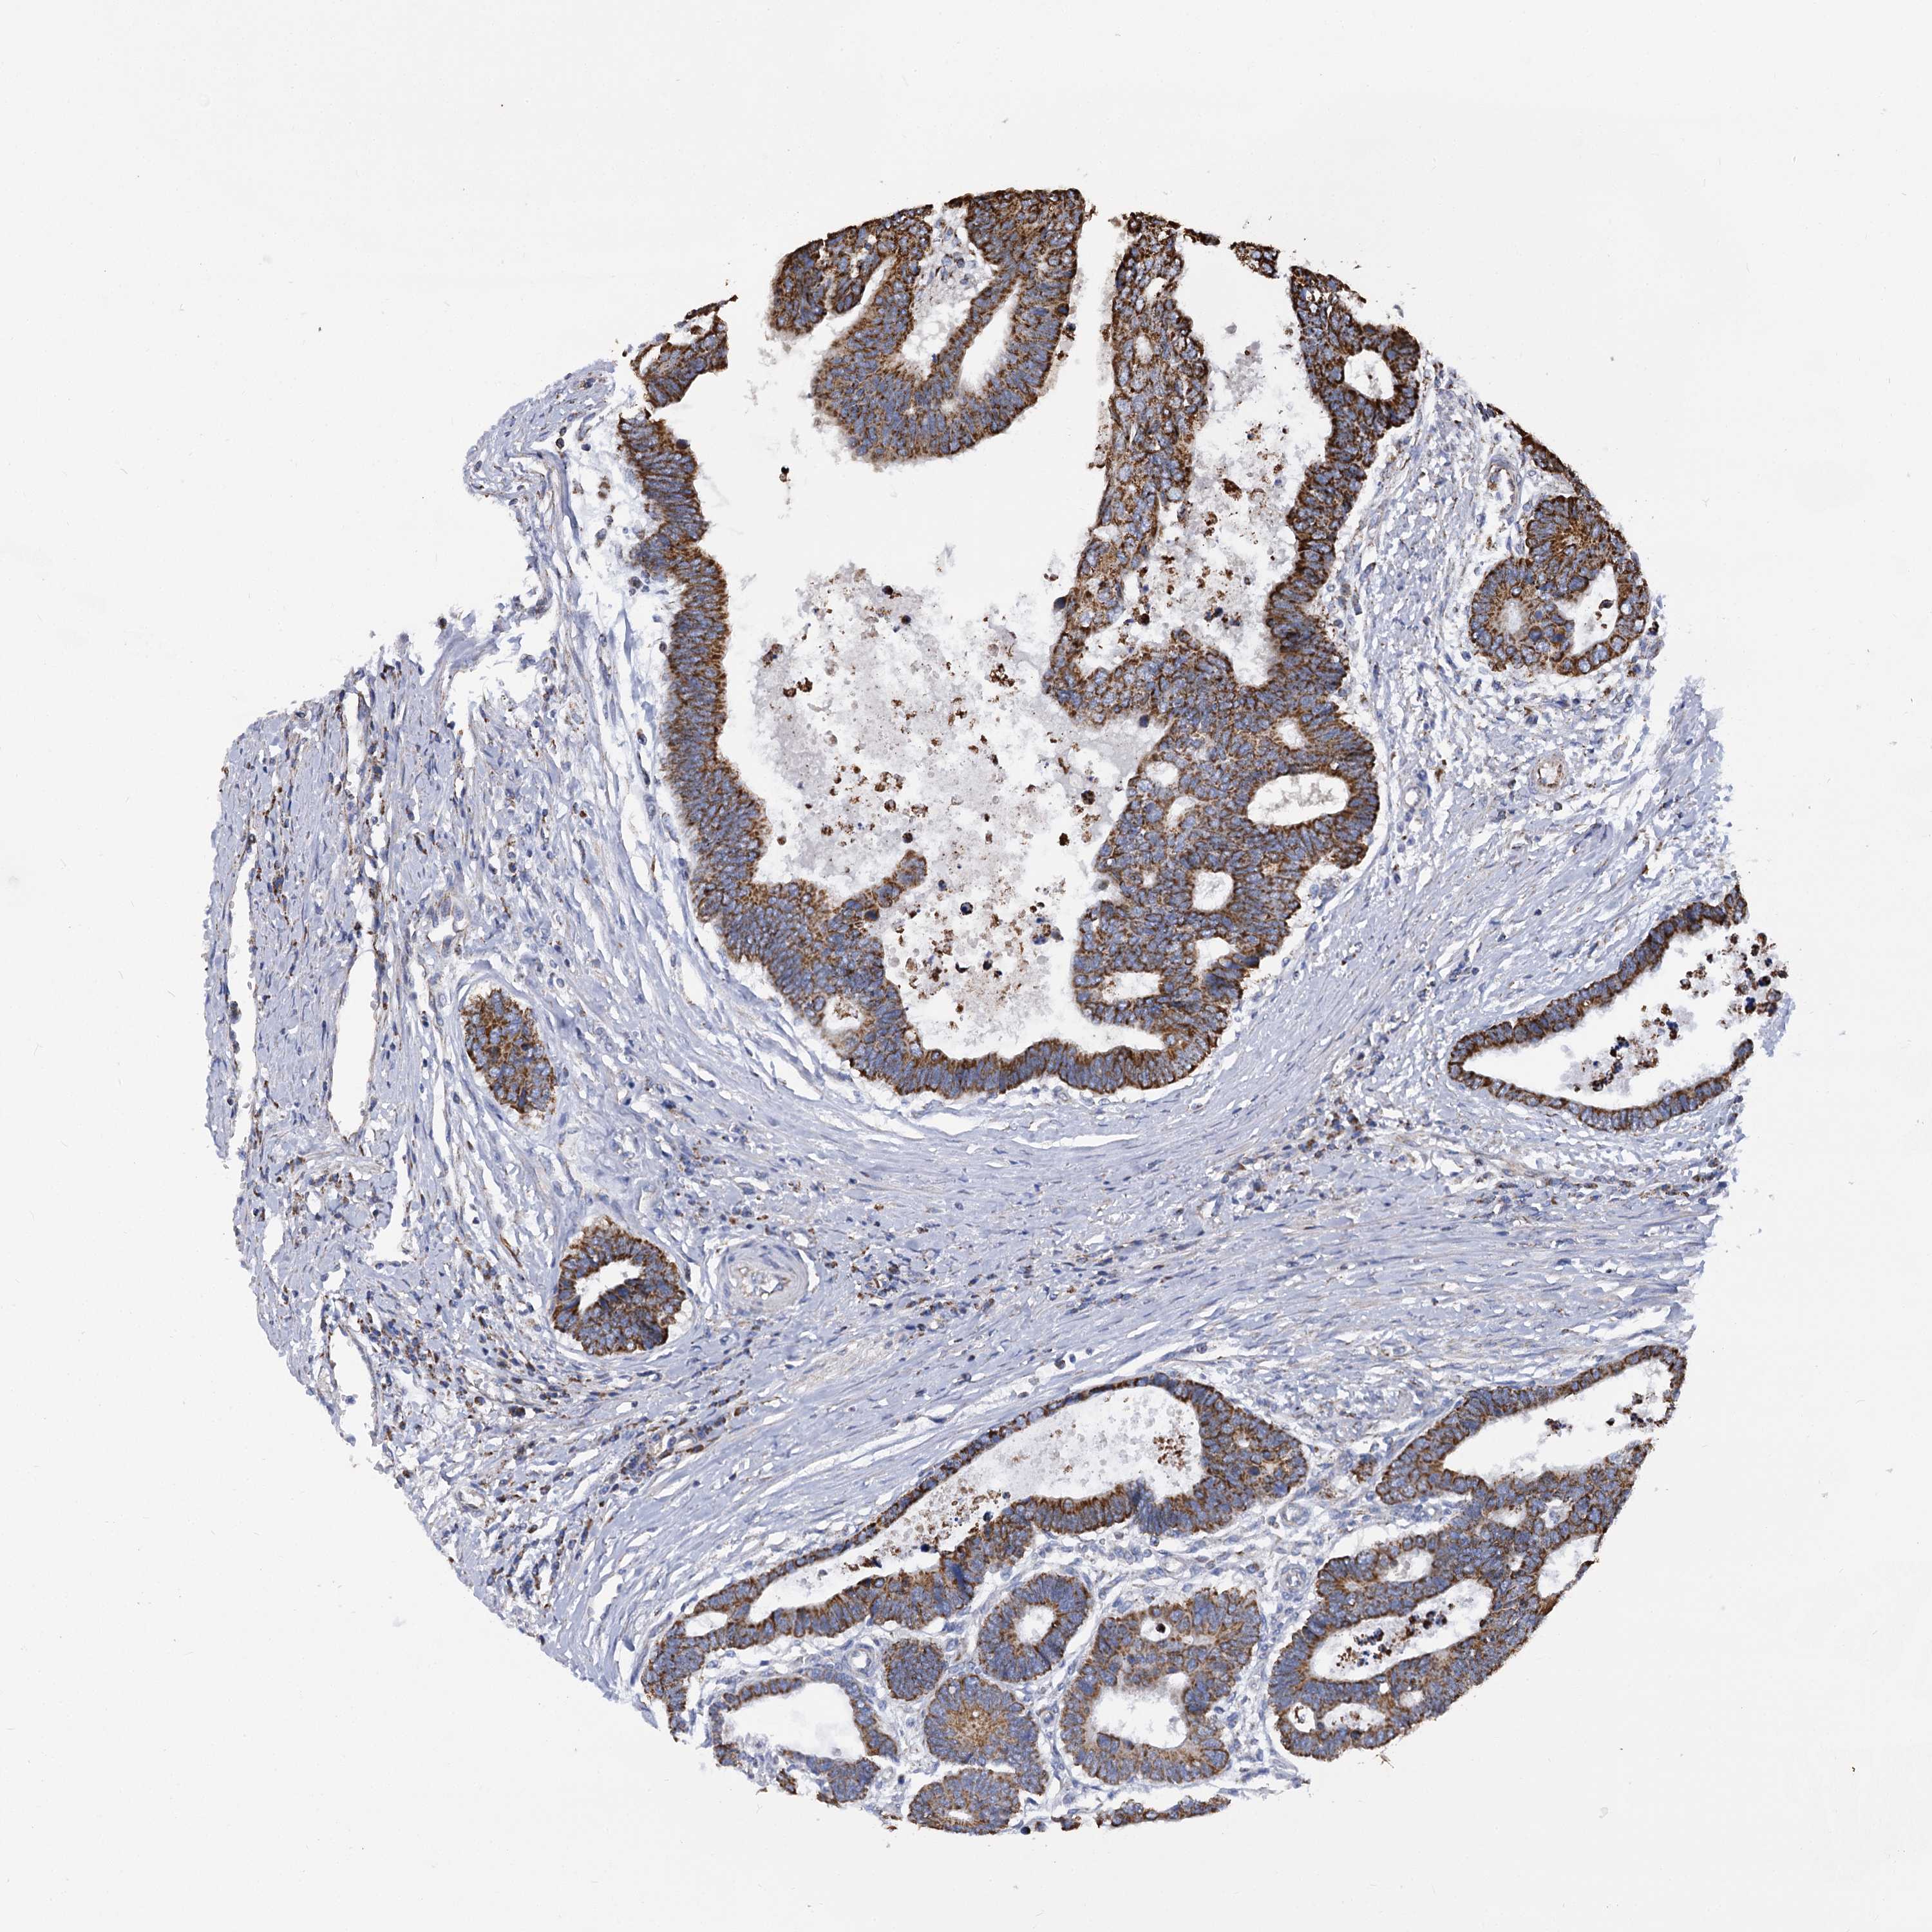

CANCER COLORECTAL CANCER Show tissue menu

Colorectal cancer

Human cancer

Colon adenocarcinoma